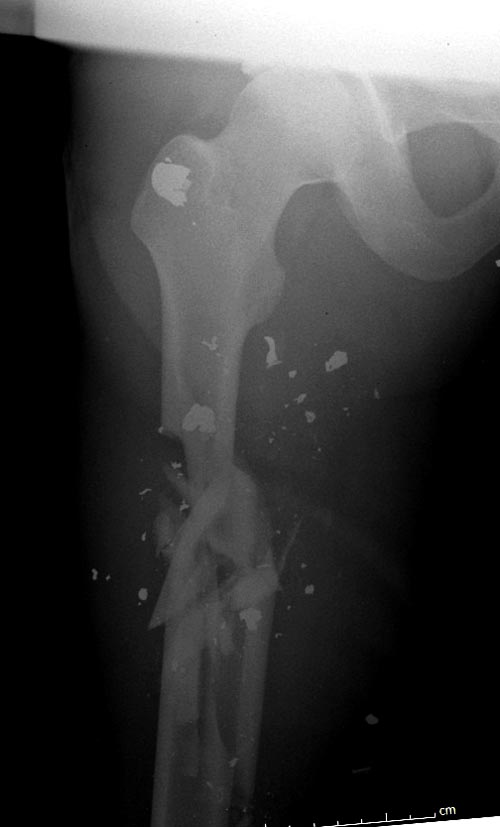

На снимках осложнение огнестрельного перелома бедра поздней инфекцией. 7

лет назад оперирован: правое бедро, сперва на ExFix, затем заменен на

гвоздь, а левая - гвоздь при поступлении.

Беспокойство проявил недавно, по поводу жалоб на боли сделано МРТ и

дренирование абсцесса терапевтами. Мы удалили гвоздь, сделали I&D,

рассверливание канала, и ввели гвоздь с антибиотиком. Для гвоздя

использовали стерильную трубку-форму, а антибиотик по 1.0 Tobramycin c

Vancomycin.